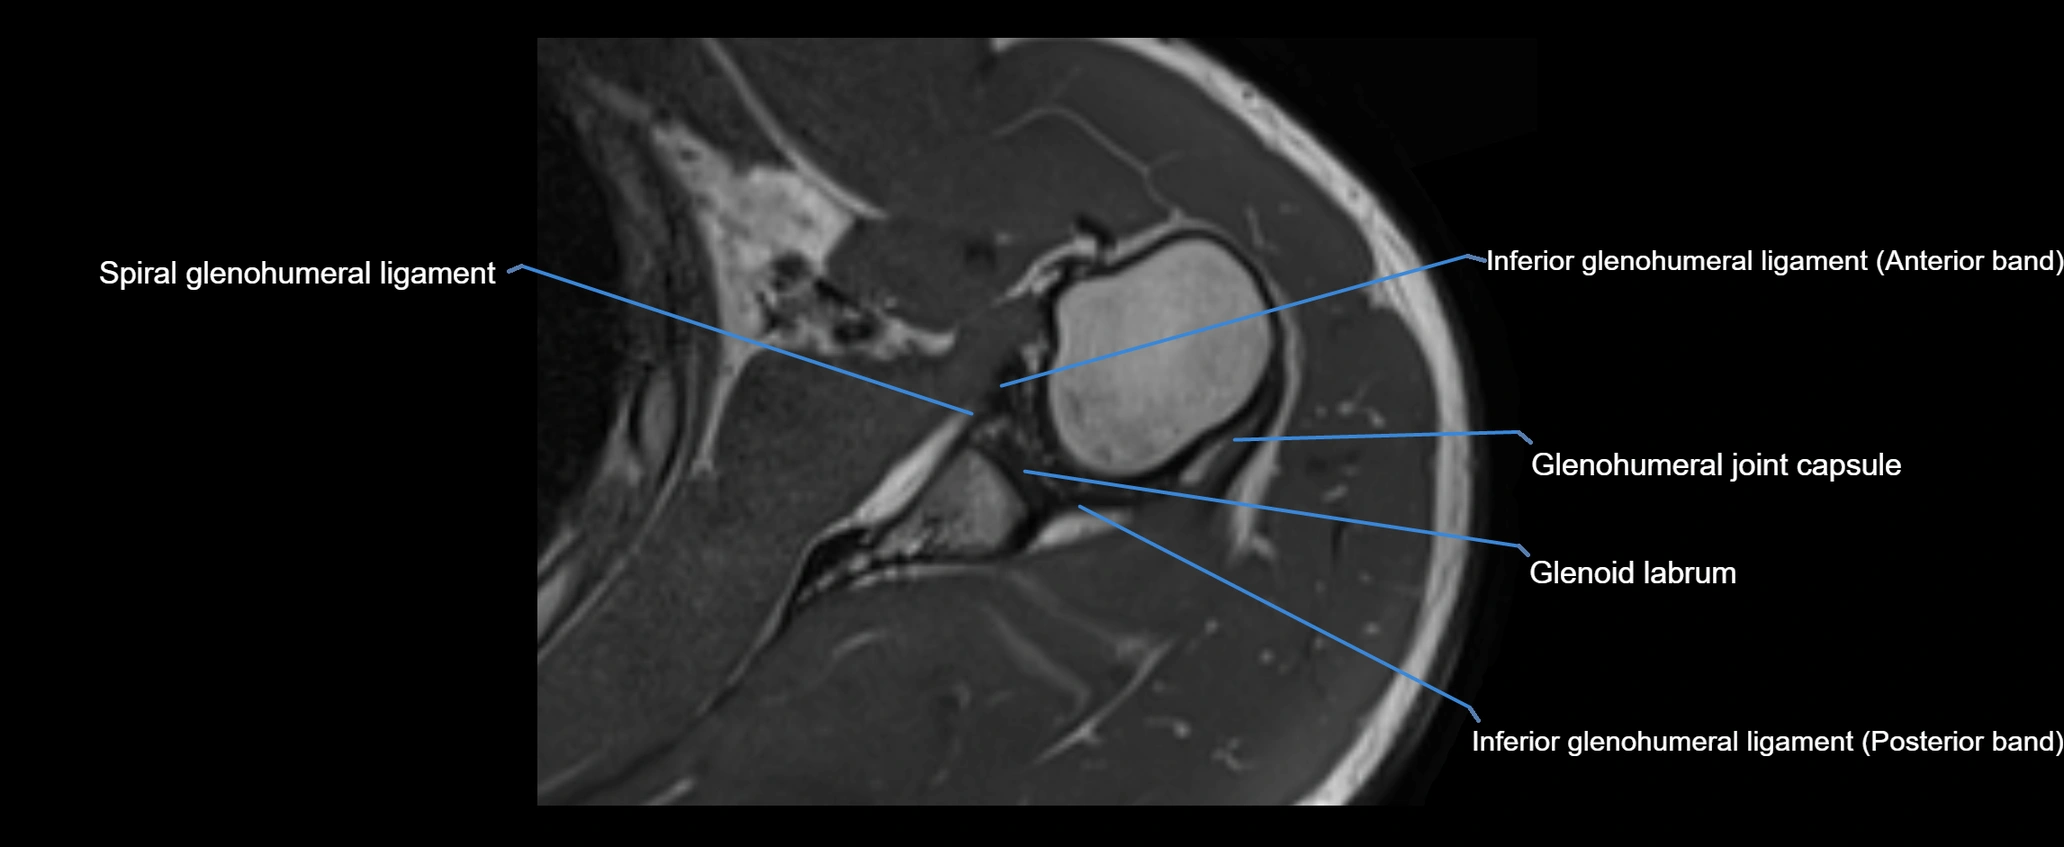

MRI images

image

MRI Appearance

• T1-weighted images:

• Normal ligament: Low signal (dark linear band) spanning acromion to clavicle.

• Surrounding fat planes: Bright, delineating the ligament clearly.

• Marrow of clavicle and acromion: Bright due to fatty content.

• Tears: Discontinuity or irregular thickening with intermediate-to-bright signal.

• Chronic injury: Thinning, fraying, or irregular low-signal fibers with adjacent scarring.

• T2-weighted images:

• Normal ligament: Low signal, homogeneous.

• Partial tear or sprain: Focal hyperintensity or thickening.

• Complete tear: Discontinuity with fluid-bright gap between clavicle and acromion.

• Associated edema: Bright signal in distal clavicle or acromion marrow.

• STIR:

• Normal ligament: Dark linear band.

• Injury or inflammation: Bright hyperintense signal in and around ligament fibers.

• Highlights periligamentous soft-tissue edema, especially in acute trauma.

• Proton Density Fat-Saturated (PD FS):

• Normal ligament: Low signal, uniform thickness.

• Partial tear or sprain: Bright signal or contour irregularity.

• Complete tear: Clear discontinuity with bright signal gap and joint effusion.

• Excellent for assessing joint capsule, coracoclavicular ligaments, and periarticular edema.